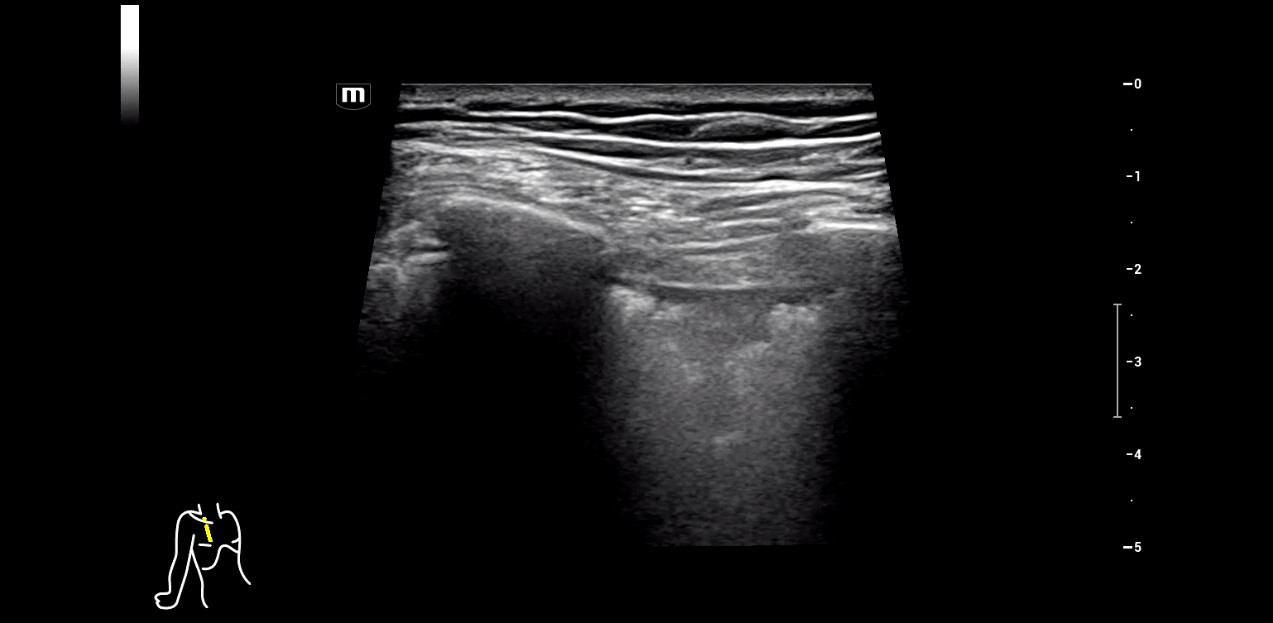

5. Residual thrombosis in the right popliteal vein. The compression test is positive in the dynamic examination.